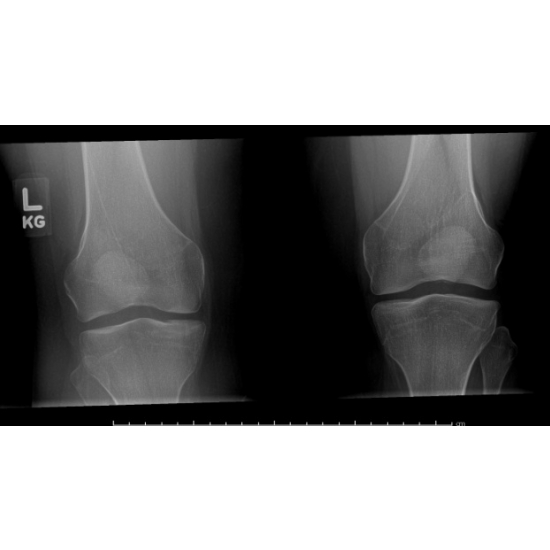

| Teenage Girl Knee-ding Some Stability - Page #3 | |||